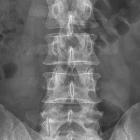

Röntgenbild

einer LWS mit Z. n. Laminektomie bei LWK 1. Der Dornfortsatz fehlt.

Z.n.

Laminektomie LWK 1 anamnestisch zur Tumorentfernung (z.B. Ependymom des Filum terminale?)